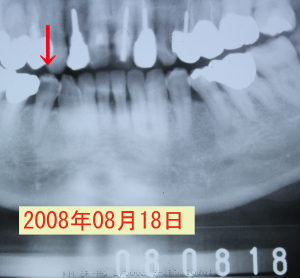

| フッ素洗口をすると、歯のしみが取れて良好。その後、来院されなくなりました。 | ||

それから3年7ヶ月後、歯がかけたと来院。 ←同部のレントゲン写真 虫歯が神経まで進行しているように見えますが、 |

| 無麻酔下で完全に虫歯に除去しても 露髄せず、神経が第二象牙質で完全に 覆われています。 |